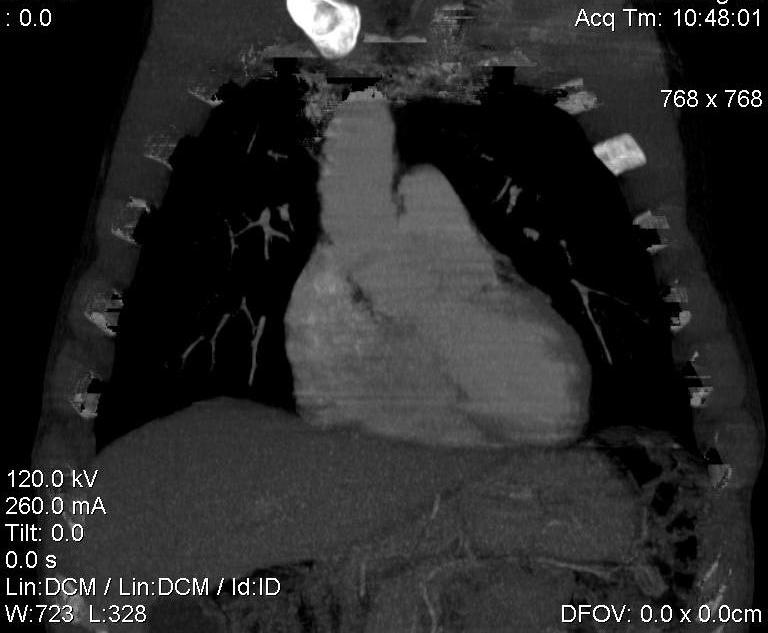

Пациент был направлен на КТ после рентгенографии ОГК, с направительным диагнозом: объёмное образование верхнего средостения.

это аномально расположенная грудная аорта

Конечно, дуга аорты идёт справа от позвоночника (декстра позиция); но есть и ещё одна аномалия той же группы: